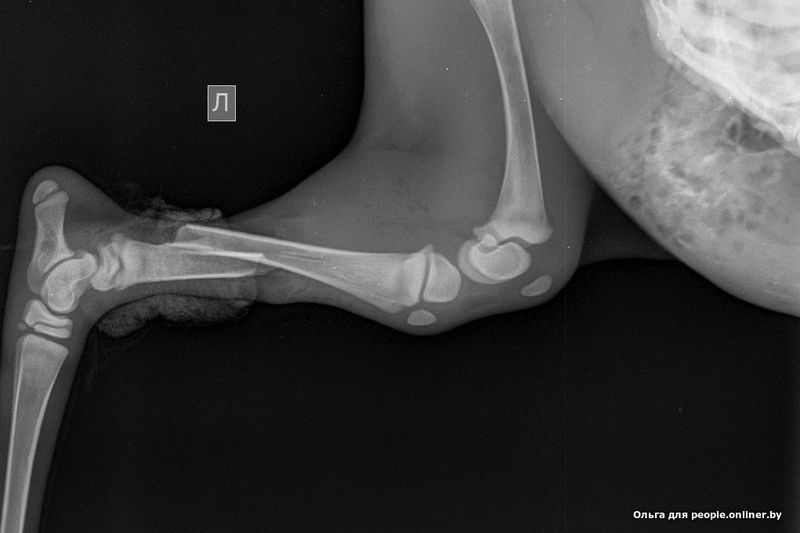

Крохотную самку весом килограмма три передали Ольге 23 июня. Но нельзя просто так забрать дикое животное и отдать гражданскому человеку, поэтому быстро оформили акт изъятия (из природы) и передачи. У детеныша на тот момент были разодраны мышцы, сломана кость, нога висела на шкуре. Ольга принялась звонить ветеринарам в Лиду. Согласились приделать ногу в ветцентре «Кот Бегемот». Вообще-то — невиданное занятие, косулям ноги приделывать, но терять все равно нечего было.

— Сначала она в шоке была, — рассказывает Ольга. — Глаза бегают, сердце колотится, ни на что не реагирует. Потом, когда адреналин отхлынул, видно, боль почувствовала — стала кричать, встать пыталась...